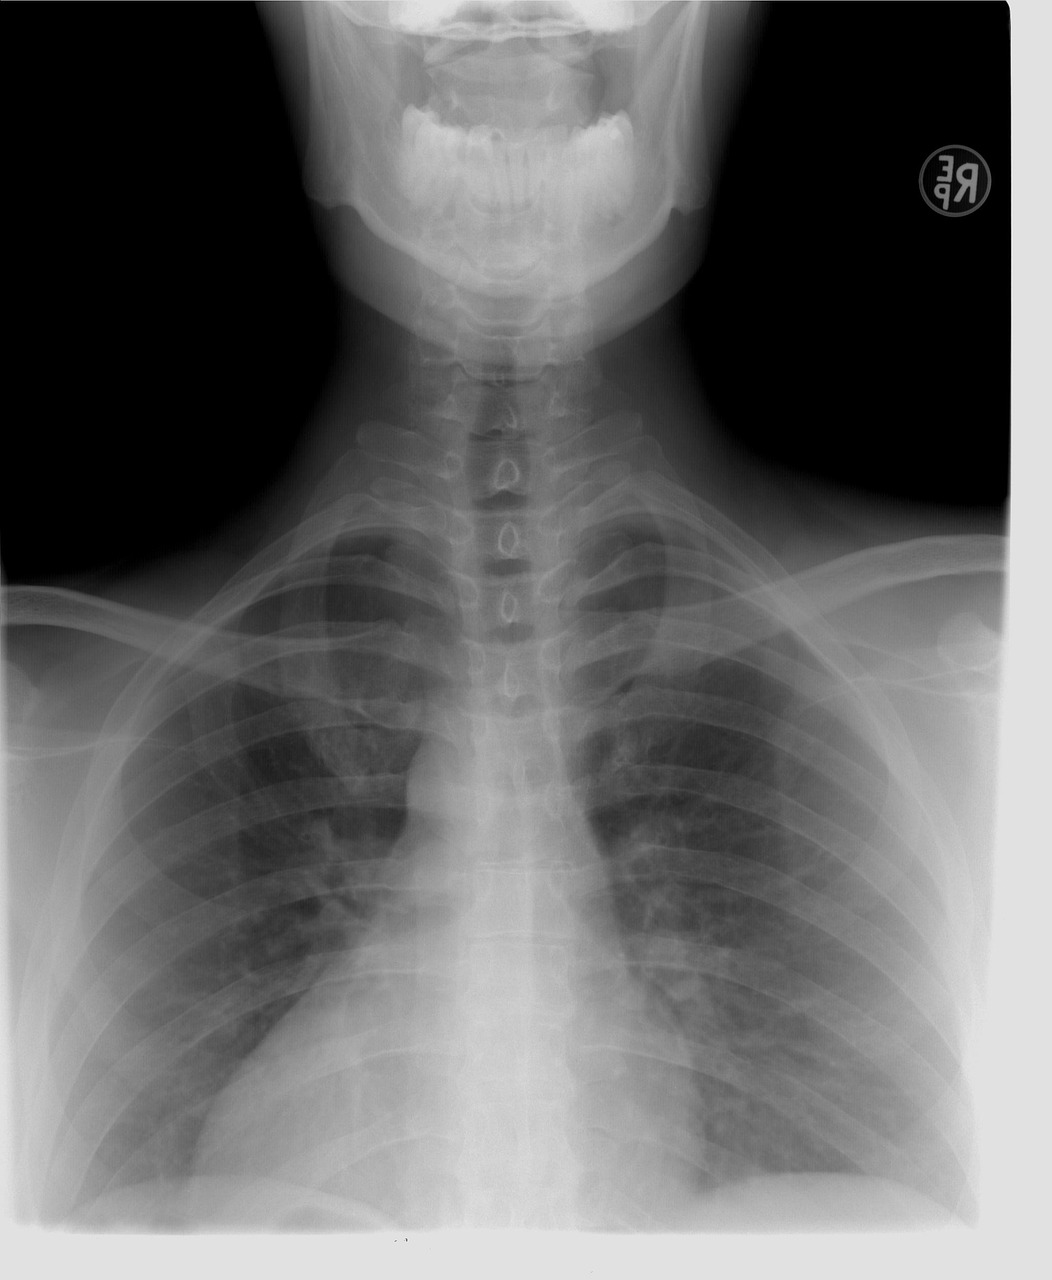

검사 방법 : 흉부 X-ray 촬영을 통해 폐에 결핵균 감염으로 인한 이상 소견이 있는지 확인합니다. 상의를 탈의하고 촬영하며, 임산부의 경우 반드시 사전에 의료진에게 알려야 합니다.

검사 목적 : 폐결핵은 호흡기를 통해 전파되는 전염병으로, 기침, 발열, 체중 감소 등의 증상을 유발합니다. 집단생활을 하거나 대중과 접촉이 많은 직업의 경우, 폐결핵 전파를 막기 위해 검사를 실시합니다.